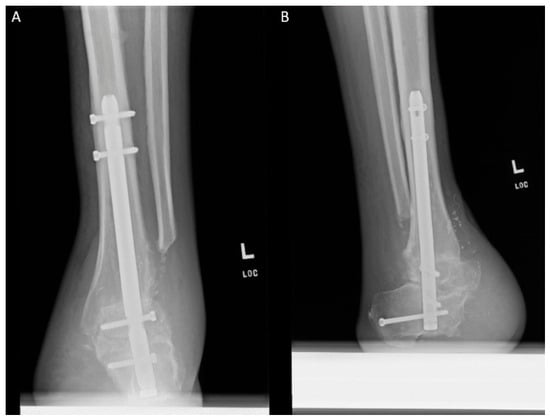

The Chopart amputation is a controversial amputation level and has been described as a relatively non-functional amputation due to the increased risk for stump deformity and subsequent complications. Recent literature has shown that a tibiotalocalcaneal arthrodesis can subjectively increase function in the Chopart amputation. We describe the use of a tibiotalocalcaneal arthrodesis in a 44-year-old diabetic male with a Chopart amputation for the purpose of limb and gait salvage. After 292 days and an uneventful postoperative course, the patient consented to gait analysis. The case allows us to objectively conclude that the tibiotalocalcaneal arthrodesis can quantitatively increase the functionality of the Chopart amputation and, in turn, expand its indication for use within the more functional populations. Full article